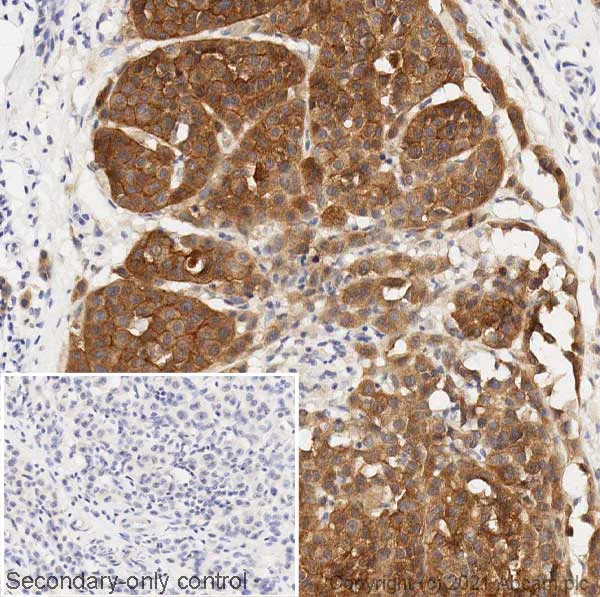

Immunohistochemistry (Formalin/PFA-fixed paraffin-embedded sections) - Anti-Ras (mutated Q61R) antibody [SP174] (AB227658)

IHC image of NRAS (mutated Q61R) staining in a section of formalin-fixed paraffin-embedded human skin melanoma* performed on a Leica BONDTM system using the standard protocol F. The section was pre-treated using heat mediated antigen retrieval with EDTA buffer (pH9, epitope retrieval solution 2) for 20mins. The section was then incubated with ab227658, 1/100 dilution, for 15 mins at room temperature and detected using an HRP conjugated compact polymer system. DAB was used as the chromogen. The section was then counterstained with haematoxylin and mounted with DPX. The inset secondary-only control image is taken from an identical assay without primary antibody.

For other IHC staining systems (automated and non-automated) customers should optimize variable parameters such as antigen retrieval conditions, primary antibody concentration and antibody incubation times.

*Tissue obtained from the Human Research Tissue Bank, supported by the NIHR Cambridge Biomedical Research Centre